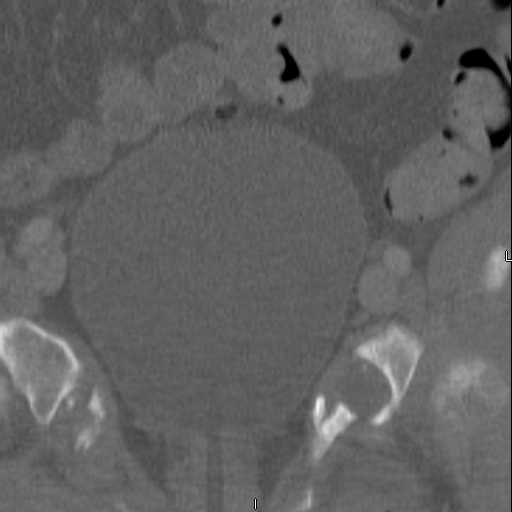

attached are images of a 59 yo female, admitted today after motor vehicle collision. Pt states her pelvis has been very painful ever since she fell on her buttocks from ground level a little over a year ago.

medical history significant for scleroderma, raynauds syndrome, and COPD. no past surgeries.

pt states she is very limited in walking ability secondary to pain. she requires a cane or a walker. friends and family do her shopping. the pain is localized primarily around left upper groin. she points to the rami region.

the question is if her medical history is contributing to the nonunions, and if anyone would consider surgical intervention, or is there some other successful intervention?